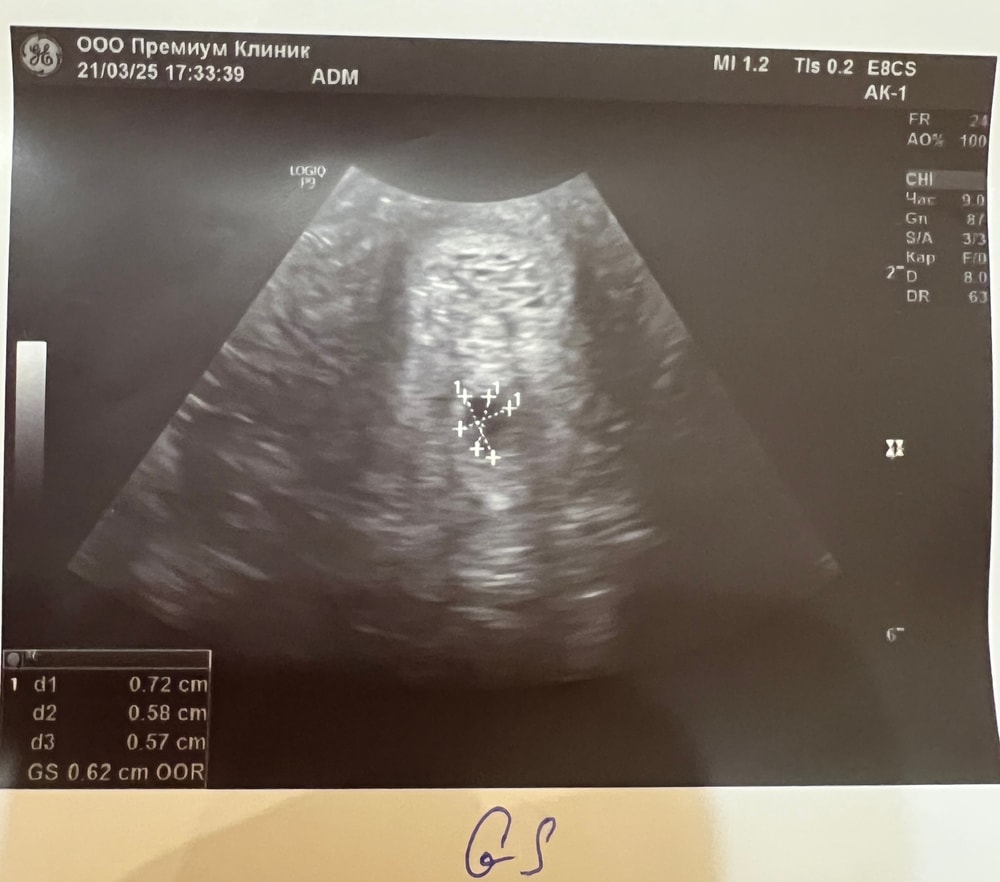

Викосик, рассказываю) нашли ПЯ Свд 6,2 мм, ктр и жм 2,2 мм. Со вторника подросло на 3 мм получается, радоваться боюсь, будем наблюдать) Изображение Изображение Изображение

Наталья, Разница между ктр и пя должна быть от 5 мм, при такой разнице как у вас, скорее всего пя остановилось в росте, а эмбрион появился вовремя. (Поэтому у вас ктр на 5.6, а пя всего лишь на 5н). В таких случаях эмбриону некуда расти, маленькое плодное яйцо его просто задавливает. При плохом росте хгч и пя плохо растет